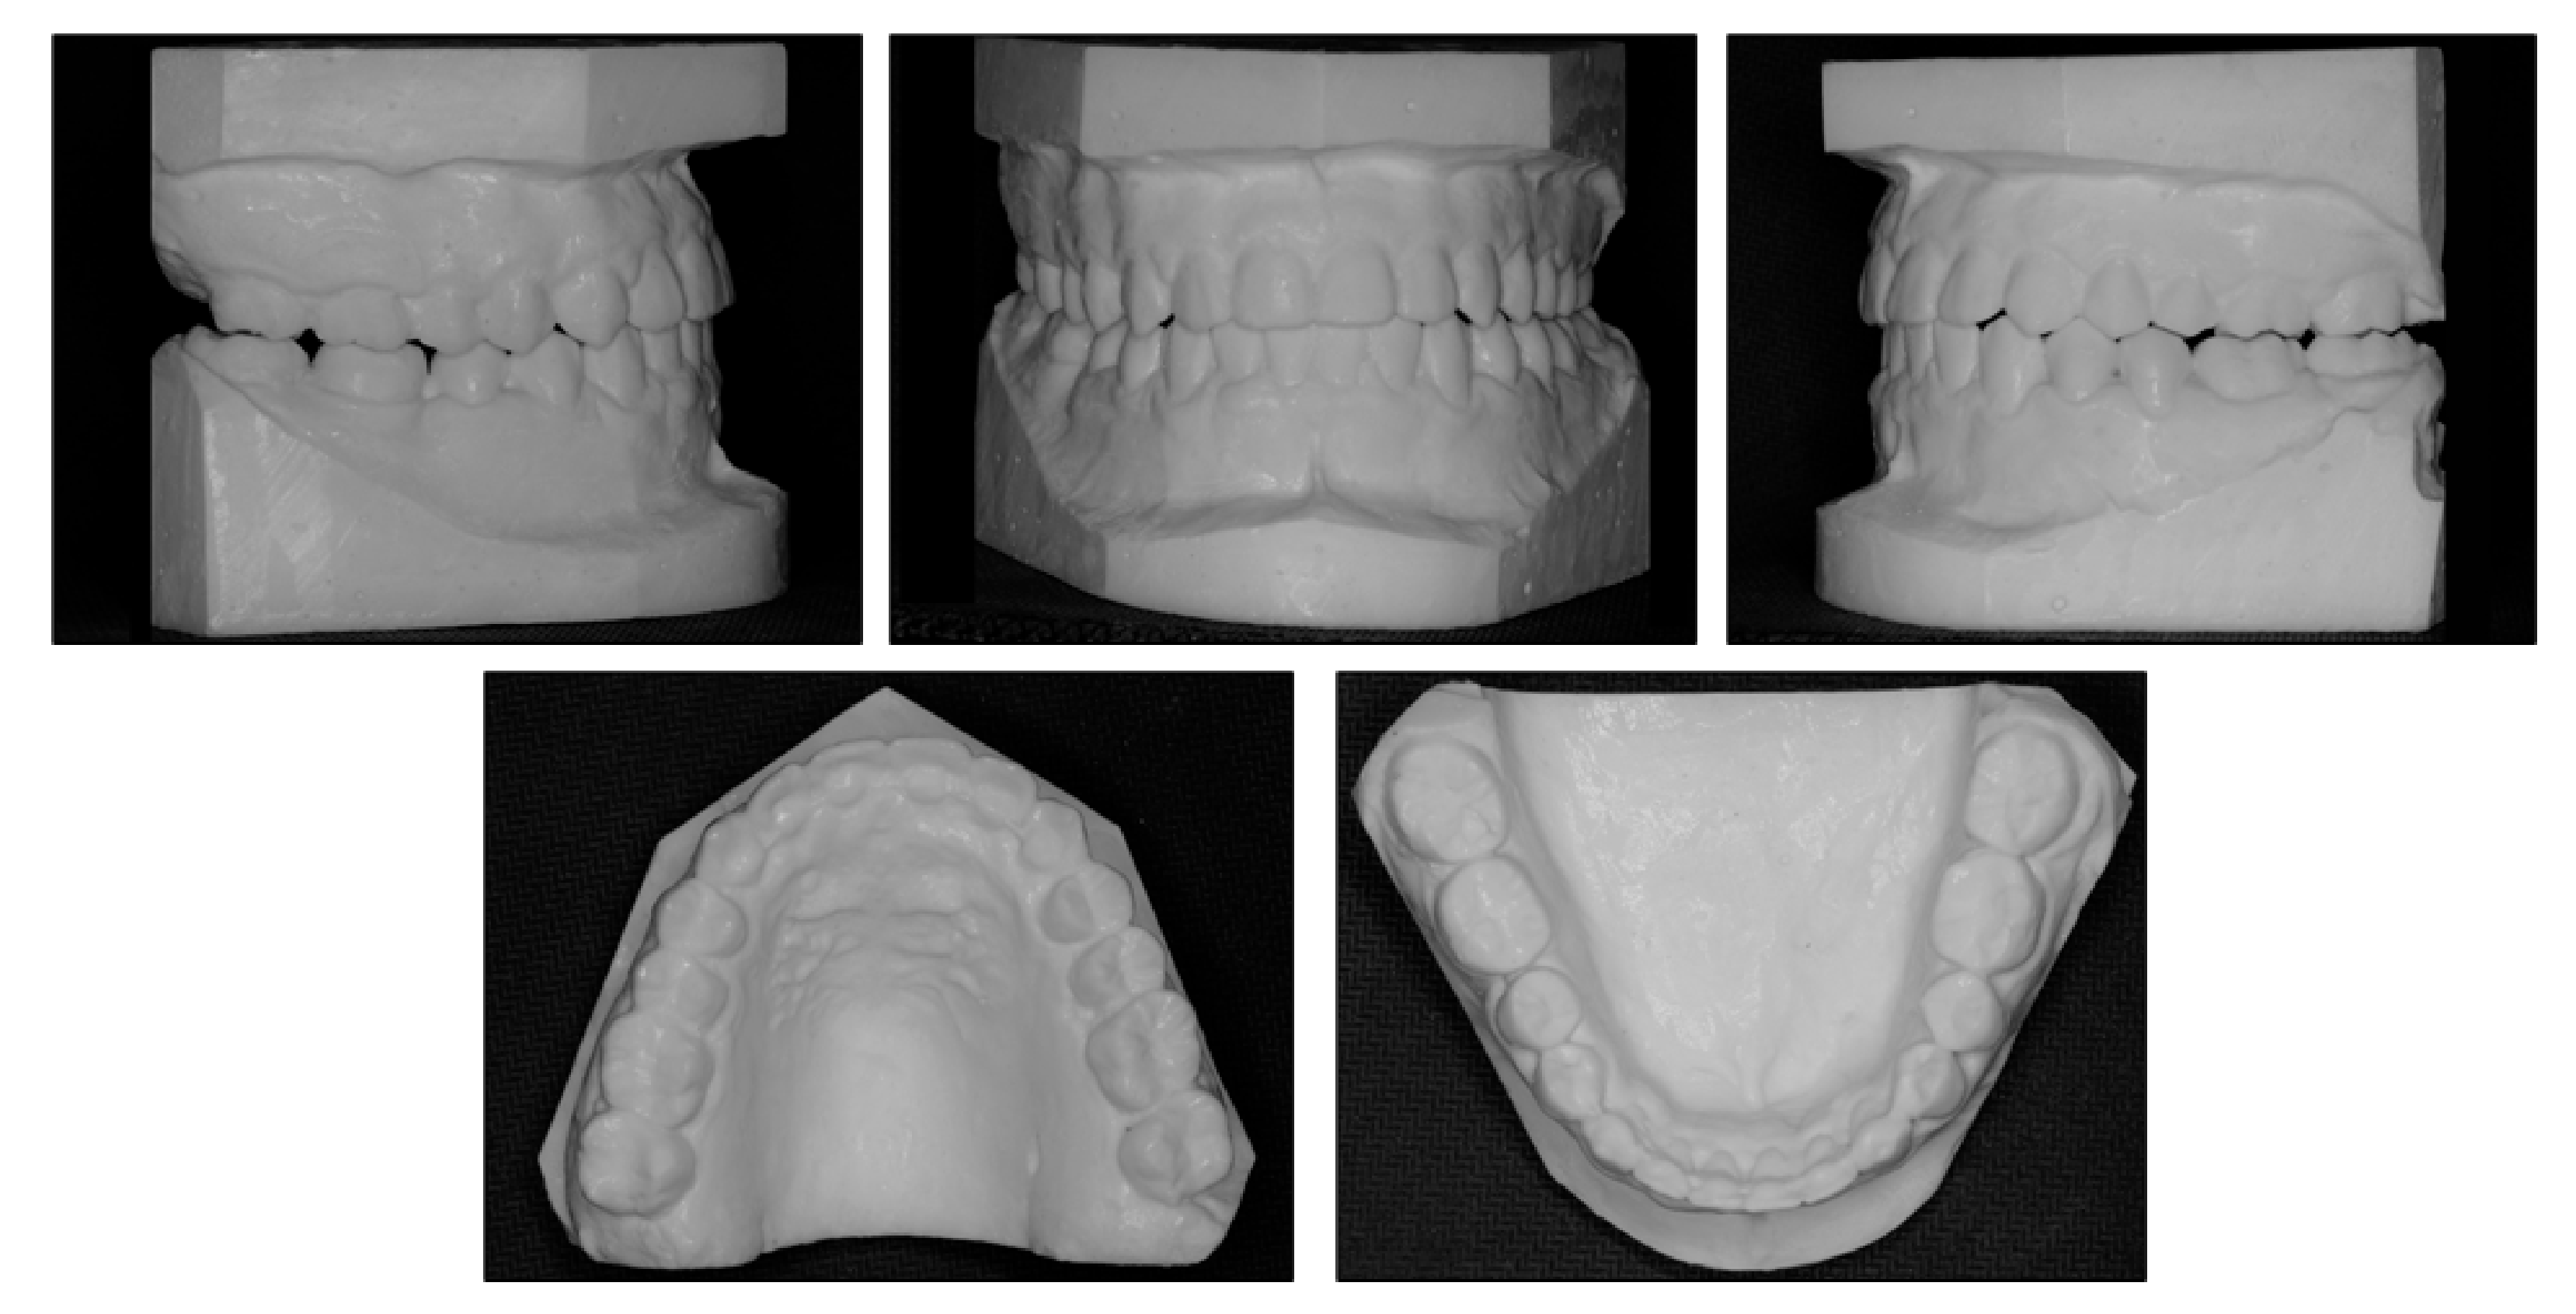

Figure 2.

Pretreatment models.

Intraorally, the patient had Class III molar and canine relationship on the right side and Class I molar and canine relationship on the left side (Figure 2). The overbite was almost zero and the overjet was −0.8 mm. There was lateral openbite on both sides, which was more severe on the left side including the canines and premolars. The mandibular left canine, premolars and first molar were in crossbite. The upper dental midline was deviated 1 mm to the right side and the lower dental midline shifted 4 mm to the left side. There was mild crowding in both arches.